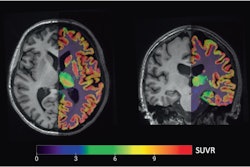

Isoprotrace is designed for prostate cancer patients and is indicated for PET imaging, for primary staging of those with high-risk prior to primary curative therapy, and for patients who have suspected recurrence based on elevated serum prostate-specific antigen (PSA) level. Isoprotrace is a single sterile vacuum-vial kit, intended for preparing multi-patient doses of gallium-68 (Ga-68) gozetotide (PSMA-11) within five minutes.